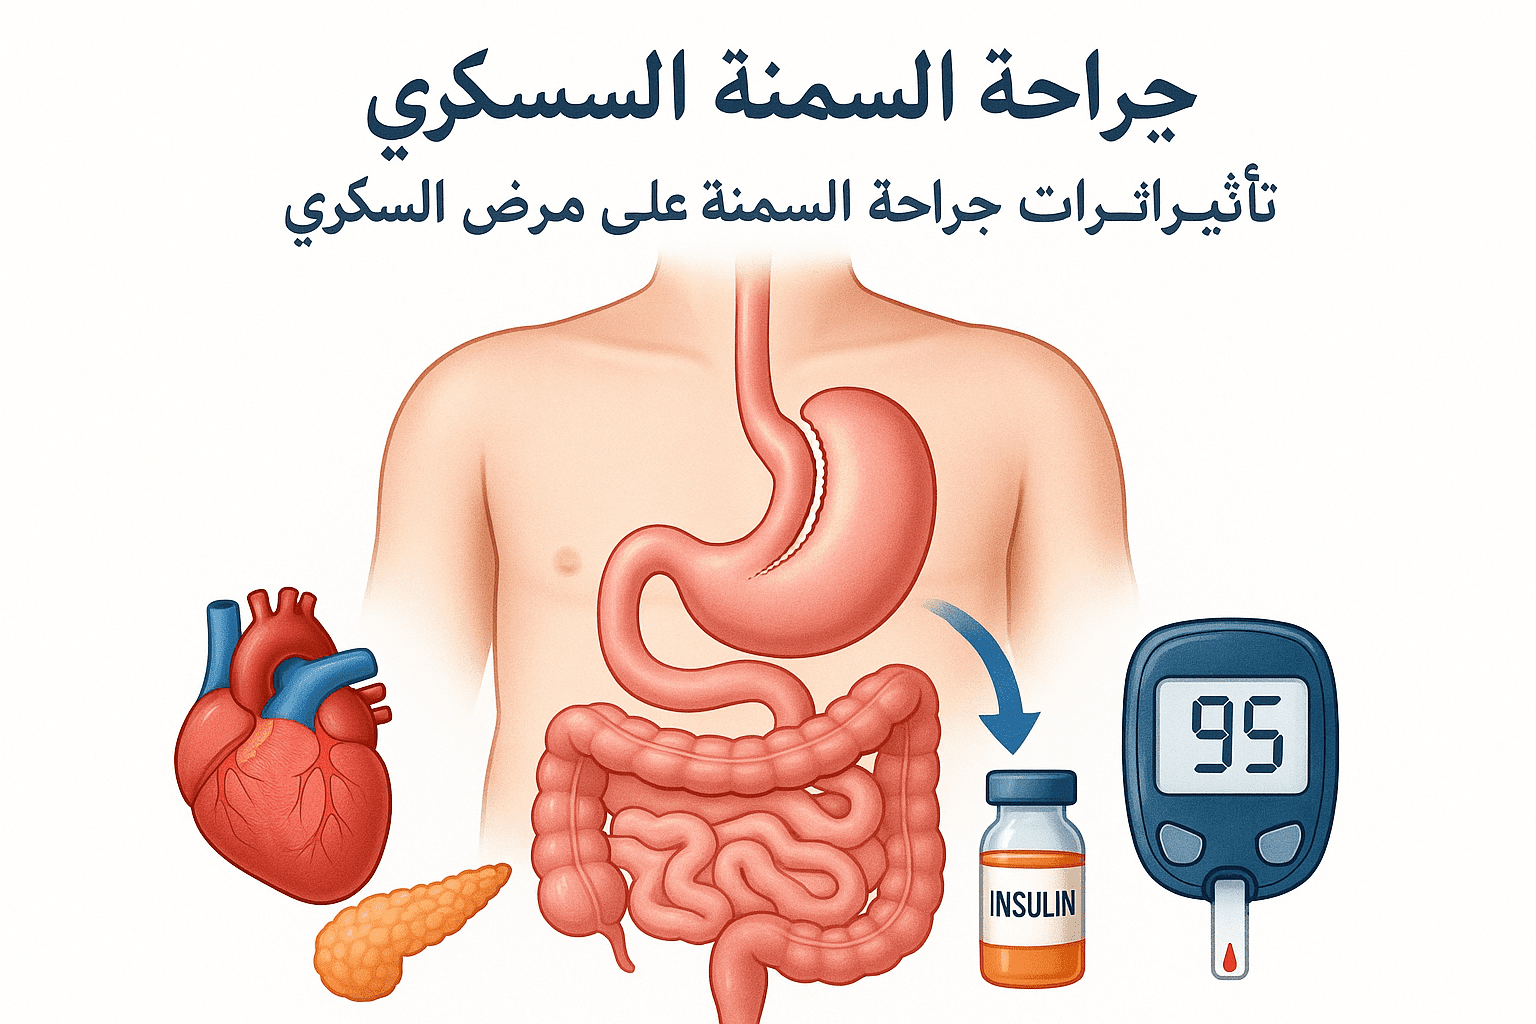

مقالات طبية من مساهمات الأطباء